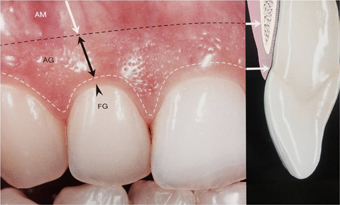

口元の美しさには、歯肉の形も関わります。生物学的幅径を保ちながら歯に適合する良い被せ物を製作しなければなりません。